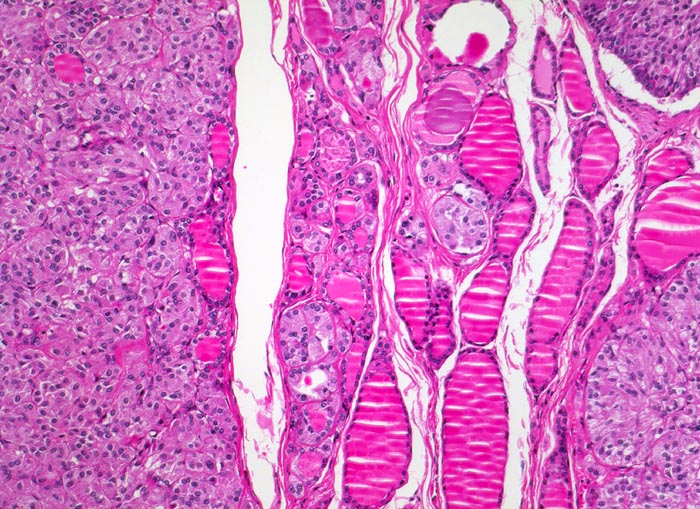

• Die Tumorinfiltrate bestehen aus soliden und kribriformen Verbänden spindeliger Tumorzellen.

• Mehrere Herde hyperplastischer C-Zellen im nicht-neoplastischen Schilddrüsenparenchym als möglicher Hinweis auf ein hereditäres medulläres Schilddrüsenkarzinom.

• Tumorzellen mit überwiegend monomorphen Zellkernen mit feinkörnigem Pfeffer und Salz Chromatin (Merkmal endokriner Zellen). Nukleolen sind nicht prominent. Reichlich eosinophiles Zytoplasma.

• Kleiner Lymphknoten mit Metastase des medullären Schilddrüsenkarzinoms. Das sollte der Kliniker dem Pathologen mitteilen: